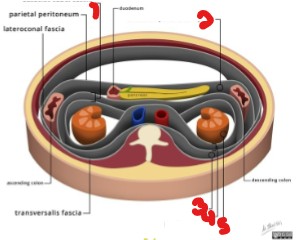

Label the renal spaces/fascia seen here.

Anterior renal fascia

Anterior pararenal space

Posterior pararenal fascia

Retrorenal fascia

Perirenal space

The pancreas is located in the (intra/retro)peritoneum.

Retroperitoneum

Inside of the retroperitoneum, the pancreas lies anterior to what?

Posterior to?

Pararenal space

The lesser sac